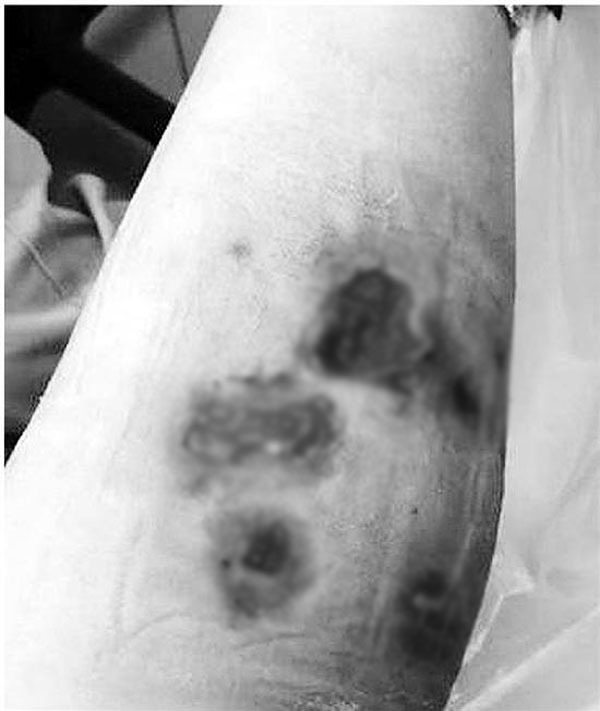

Hình ảnh vết thương trên chân của Tiểu Lý

Sau một tuần, trình trạng được cải thiện nhưng nhanh chóng tái phát trở lại. Lúc này, điều trị bằng kháng sinh không có kết quả, hai chân của Tiểu Lý xuất hiện vết loét, mủ, vùng da và mạch máu xung quanh chuyển sang màu đỏ tím.

Lúc này, Tiểu Lý đã đến bệnh viện để điều trị. Tuy nhiên khi nhập viện, các bác sĩ không tìm được nguyên nhân khiến chân Tiểu Lý bị nhiễm trùng, hoại tử. Sau gần một tháng, các chuyên gia mới xác định trực khuẩn mà cô gái trẻ nhiễm phải, đó là Mycobacteria không điển hình. Chúng có thể gây nhiễm trùng da và phổi ở những bệnh nhân có hệ miễn dịch thấp.